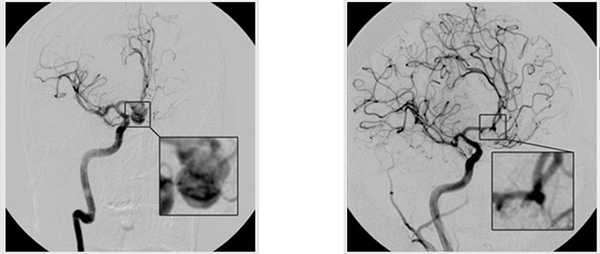

техника клипирования аневризмы головного мозга

аневризма до/после операции